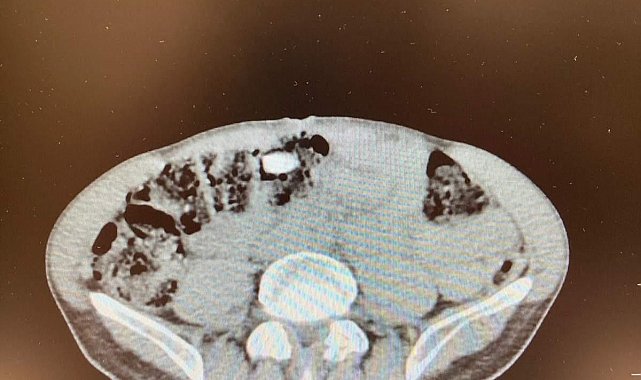

Denizli İl Emniyet Müdürlüğü Narkotik Suçlarla Mücadele Şube Müdürlüğünce uluslararası uyuşturucu madde ticaretinin önlenmesine yönelik çalışmalar devam ediyor. Yapılan incemeler ve değerlendirmeler sonucunda Denizli'ye havayoluyla yolculuk eden yabancı uyruklu şahsın uyuşturucu madde getireceği tespit edildi. Şüpheli, Narkotik Suçlarla Mücadele Şube Müdürlüğü ve Çardak Havalimanı Gümrük Muhafaza Bölge Amirliği görevlilerince müşterek yapılan çalışmalar neticesinde yakalandı. Şüphelinin eşyalarında yapılan aramalarda 6 parça halinde giysilere emdirilmiş şekilde 1 kilo 257 gram metamfetamin maddesi ele geçirildi. Yapılan iç beden muayenesinde ise 3 parça halinde 15 adet ecza hap ele geçirildi. "Uyuşturucu veya uyarıcı madde ticareti yapmak" suçundan adli makamlara sevk edilen şüpheli, tutuklanarak cezaevine gönderildi.